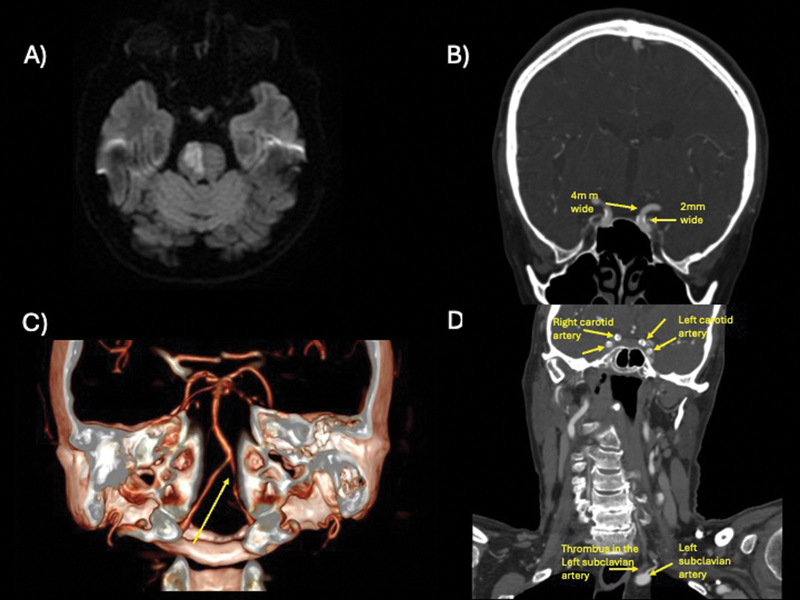

Chessboard stroke attributed to intracranial atherosclerosis.

颅内动脉粥样硬化导致棋盘状中风。